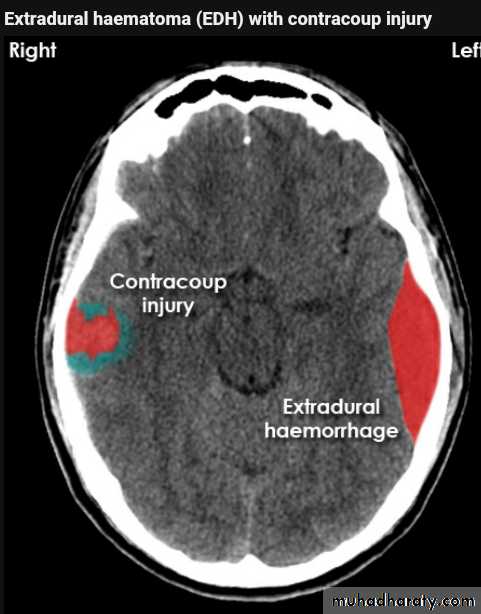

Acute EDH

CT finding

Hyper density area, 50-70 HU, due to the clotted blood, elliptical in shape, no edema around the lesion, but may cause shifting of the midline, or compression of the ipsi lateral ventricle if it is large enough.

The source of bleeding of the haematome is injured middle meningeal artery so the lesion > 90 % associated with skull # at the site of the previous mentioned artery.

EDH

Biconvex hyper density area

Shifting of the midline

Compression of the ventricles